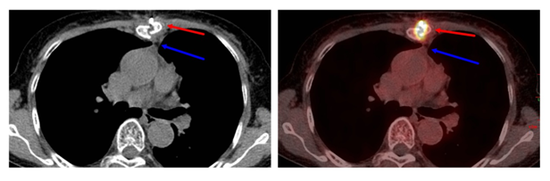

进行PET/CT检查后,医生通过PET图像、CT图像、PET/CT融合图像的阅片,胸骨呈术后改变,术区未见明显病变及显像剂的异常摄取,未见复发或残留(图2);右肺野近胸膜下可见多个边缘模糊的小结节,与前次CT片比较病变缩小,没有显像剂的异常摄取,符合良性病变。同时,发现宫颈处有斑片状的异常显像剂摄取,密度没有异常,考虑占位性病变(图3)。诊断医生再次询问李阿姨及家属,患者于48岁停经,目前没有异常引道流血等妇科症状,建议进行妇科检查。之后完成盆腔磁共振检查及宫颈活检,病理诊断为宫颈鳞状细胞癌,临床分期为IIA2期,经院内多学科会诊,依据诊疗规范,首选同步放化疗+阴道后装放疗的治疗策略。通过PET/CT检查,发现了胸腺瘤之外的第二原发恶性肿瘤,体现了PET/CT检查的高敏感性、高准确性,为临床更好地采取规范诊疗措施提供依据。

图2:红箭:胸骨术后改变;蓝箭:术区未见病变及异常代谢